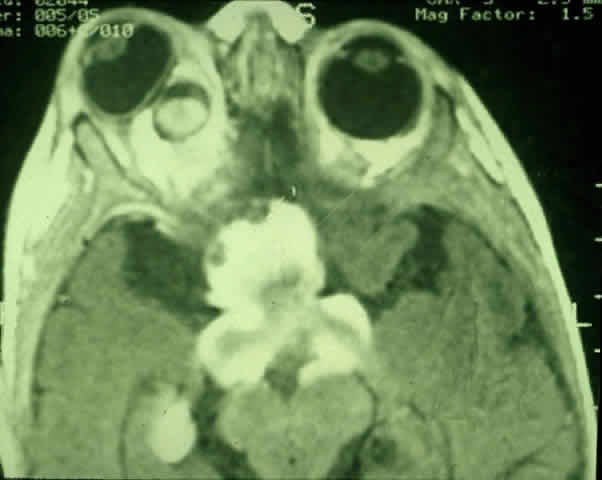

MRI has replaced CT scanning as the optimum test for imaging optic gliomas (Fig. 4 A and B). Optic gliomas have normal to slightly prolonged T1 relaxation times and appear isointense to slightly hypointense to normal brain on T1. Because many of these tumors have prolonged T2 relaxation times, images that are T2 weighted may be used to assess gross tumor margins and posterior extension.72 Optic nerve gliomas often demonstrate minimal enhancement after administration of contrast. To improve MR imaging of optic nerve lesions, a gadopentetate dimeglumine enhancement technique combined with fat suppression can be utilized. Unlike meningiomas, the thickened sheath from arachnoid hyperplasia associated with gliomas will not enhance.77 Although imaging should initially be performed in the axial plane to allow visualization of both the optic nerve and the posterior optic pathways, sagittal views are helpful in demonstrating chiasmal involvement; coronal views can be utilized to delineate intracanalicular tumor.78

Fig. 4. A. T1-weighted sagittal MRI of a patient with neurofibromatosis type 1, demonstrating enlarged optic chiasm consistent with optic glioma. B. T1-weighted coronal image with gadolinium and fat suppression in the same patient, demonstrating the chiasmal glioma.